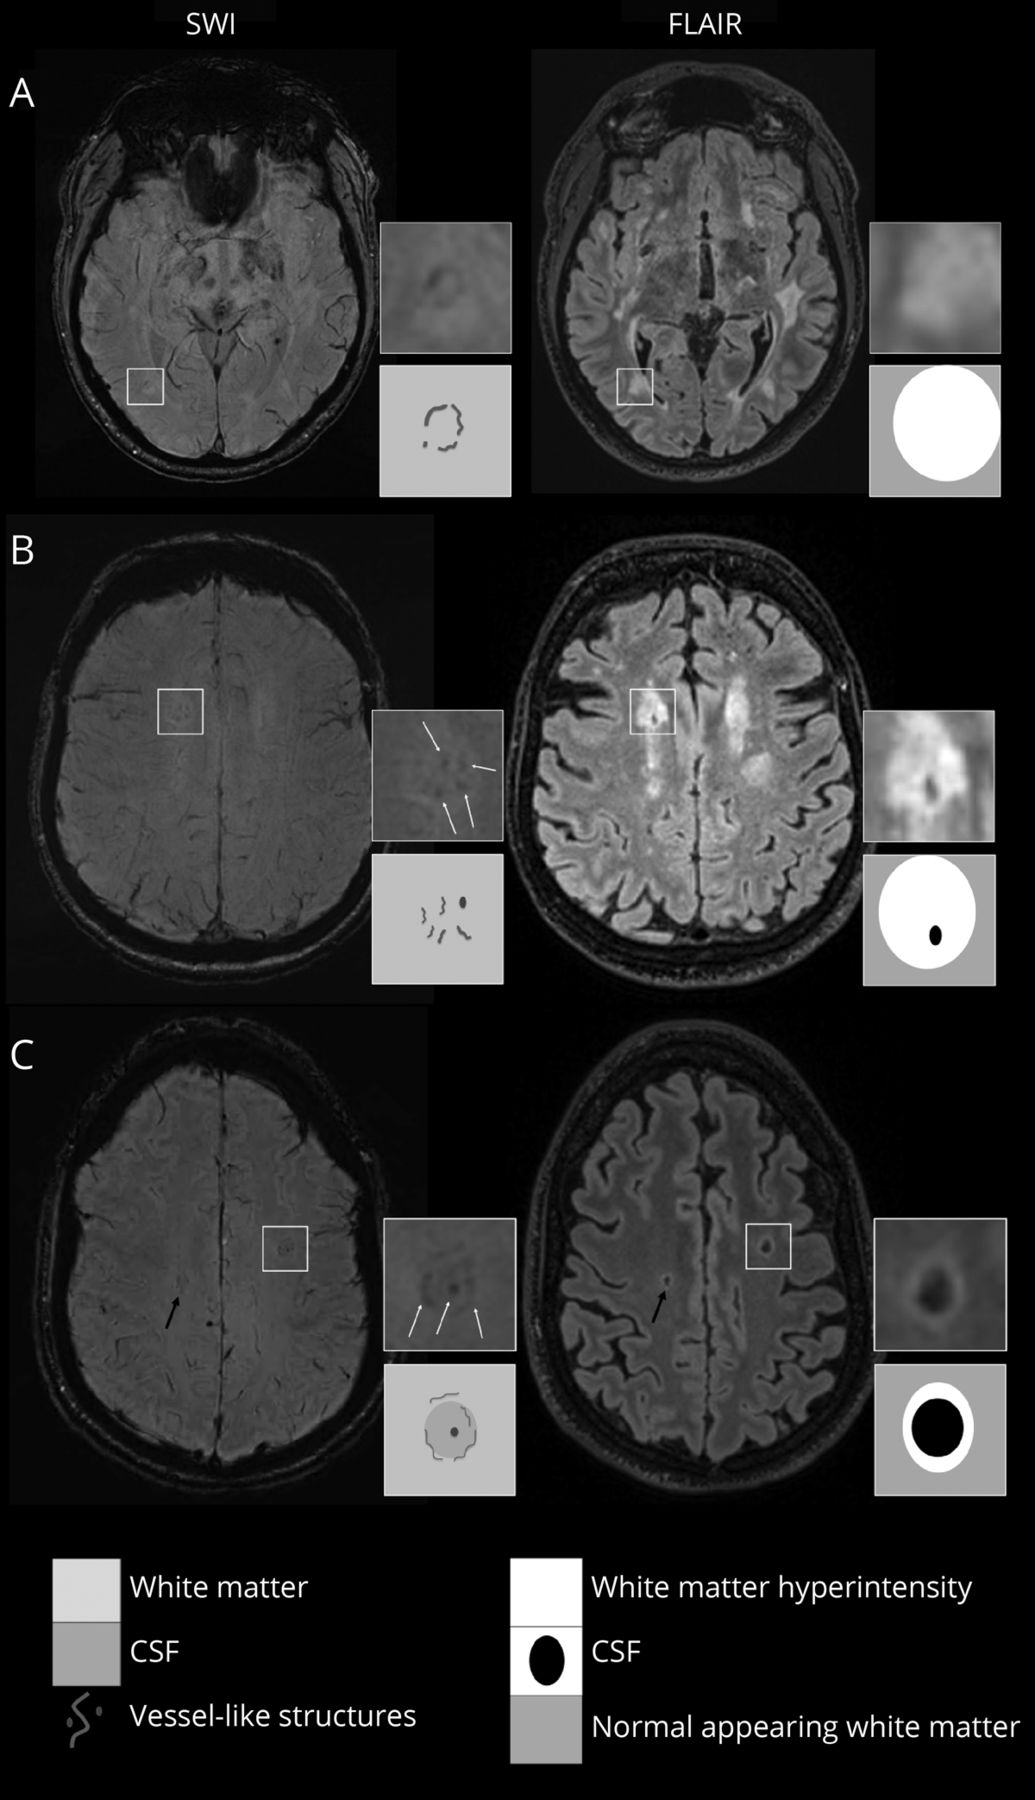

Vessel-clusters表示在广场(4 x)来显示增强的细节susceptibility-weighted成像(瑞士)和fluid-attenuated反转恢复序列(天赋),另一个不是增强vessel-cluster黑色箭头(C)表示。对于每个病人(与CADASIL B和C,零星的计算,我们现在最翔实的瑞士(左)和相应的天赋(右)序列显示vessel-cluster外观。Vessel-clusters具有集群小管状结构,可见低信号点(B和C)或线(A、B和C)在瑞士不是对应正常深髓静脉(可见轻度低信号平行线达到深层白质的侧心室)。Vessel-clusters白质内看到hyperintensities不同等级的空化:没有(一个),部分(B),或完成(C)空化。的示意图外观vessel-clusters瑞士和等级的空化天赋在相应方格表示对应的下面。圣言会=小血管疾病。

我们定义为“vessel-clusters”分组小tubular-like低信号结构的出现在瑞士(视为点或线的取向取决于参考轴面)在白质(图1),出现像小型船舶,但现在混乱分布与大型深髓静脉与正常相比出现在瑞士(eFigure 1,links.lww.com/WNL/C29)。12因此,“vessel-cluster”的定义是基于其放射的外表,虽然这样的本质在病理研究中发现可能需要进一步确认。

我们描述的位置vessel-clusters指的空间关系与前部和侧脑室后角(前部、中部和后部白质),如前所述,13以及是否vessel-like结构出现的边缘线性边缘白质空化。体积(毫升)和形状(圆形、卵圆形、线性或不规则)的大脑区域的覆盖每个vessel-cluster分割后评估感兴趣的区域(eMethods,links.lww.com/WNL/C29)。相对应的大脑区域的特点vessel-clusters评估结构序列(天赋,T1w、T2w)和分类的基础上,以前的工作14:正常白质,noncavitated负责人,部分形成空洞负责人(花边外观或不完整的蛀牙与残余的组织),并完全包含CSF-like液体形成空洞病变。集群的一些例子和相关组织在结构序列所示图1。